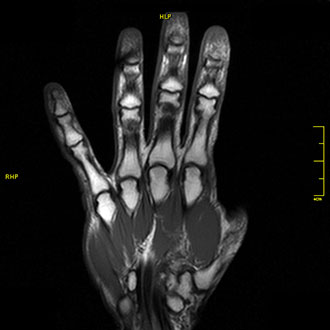

Die MRT der Finger zeigt Traumafolgen, Arthrosen (z. B. bei Rheuma) sowie Verletzungen der Streck- und Beugesehnen.

Durch die hohe Auflösung lassen sich selbst kleinste Strukturen exakt beurteilen – wichtig für die präzise Diagnostik bei schmerzhaften oder eingeschränkten Fingergelenken.